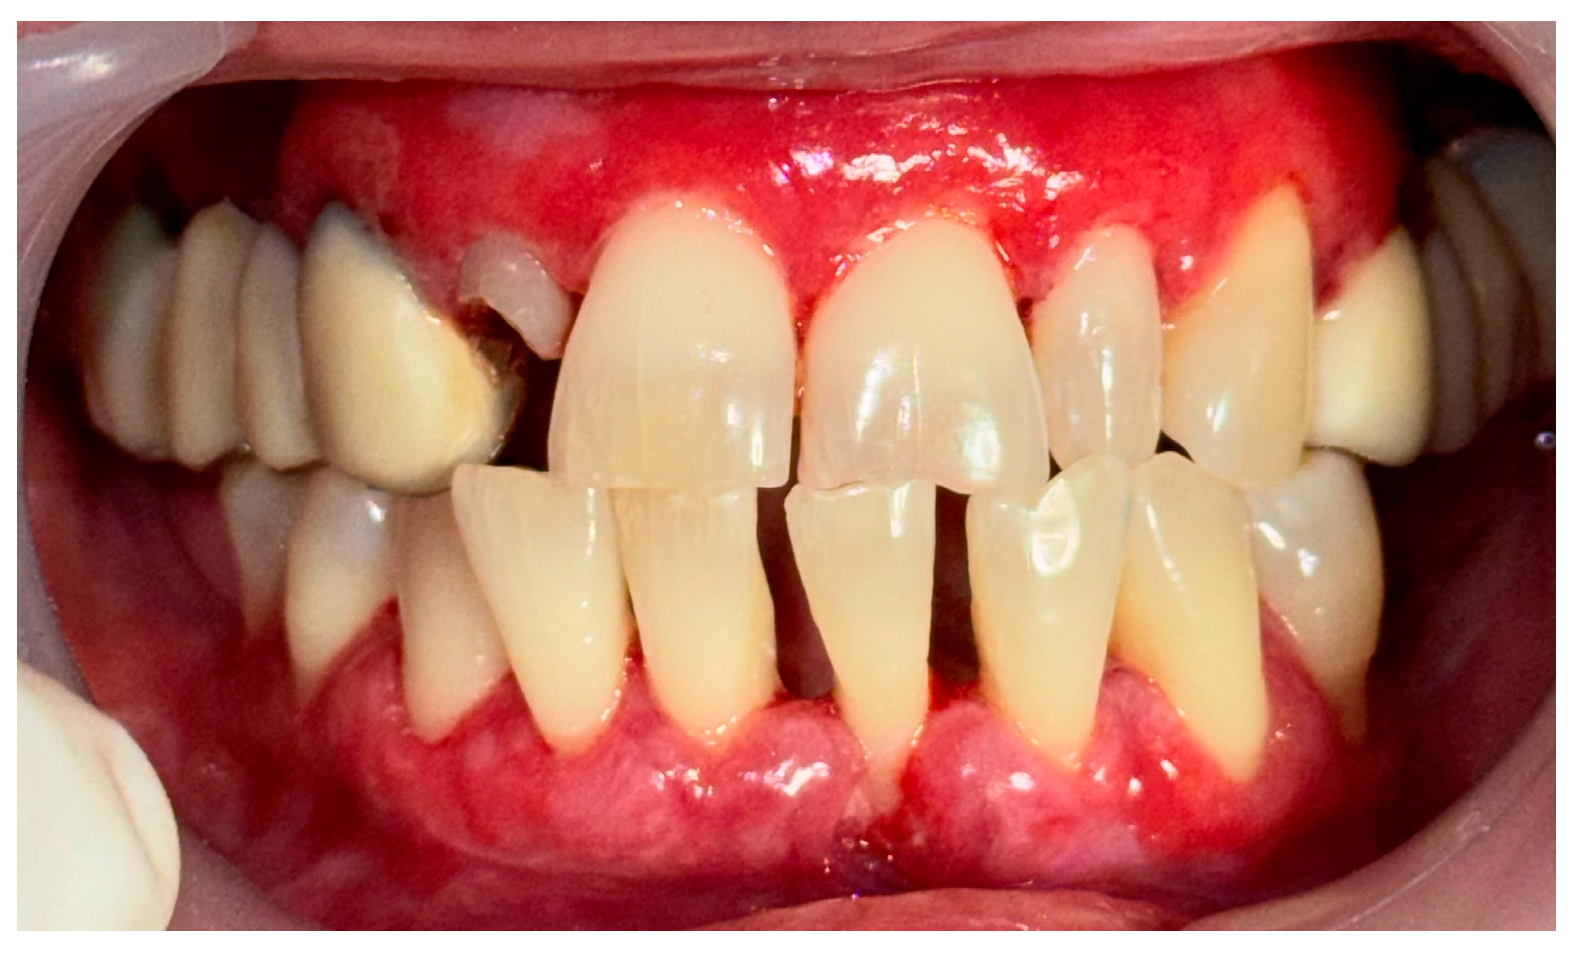

2.3. Clinical Case 3—Oral Lichen Planus (OLP)